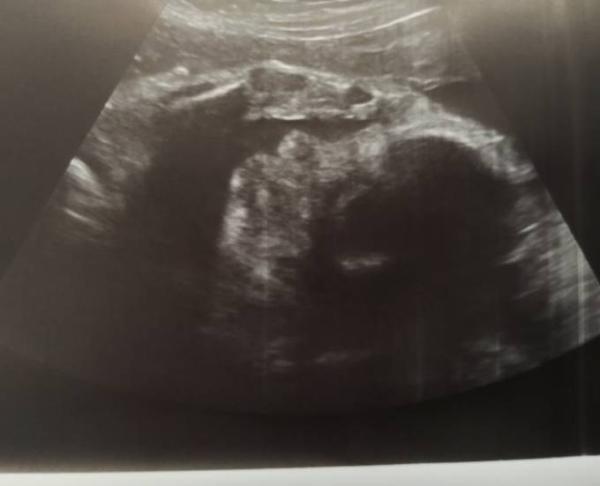

Hi Mädels, Gestern früh war Besuch bei der neuen fä angesagt, mein Freund war das erste Mal dabei bei der neuen, ich war zum zweiten Mal dort. Auch er sagte, dass sie nicht mit uns auf einer Wellenlänge ist und er sie nicht so sehr mag, wie meine letzte, naja das habe ich ihm ja selbst schon nach dem letzten Termin gesagt. Jetzt ist es so, ich wollte, dass sie gestern mir das dritte screening für den Mutterpass macht, da ich in zwei Wochen nicht kann und was vergisst sie, das in mein Mutterpass zu schreiben ich war so genervt gewesen.. Erst recht, da ich ja dann abends nochmal hin fahren musste um es nachzutragen ich hab sogar vorher angerufen und hab gefragt ob es geht das nachtragen zu lassen, auch wenn meine Ärztin nicht da ist und ich bekam dreimal gesagt, dass es geht, ja ich suche ein Parkplatz laufe da hin und dann die Dame am Empfang: nein das geht nicht, das macht normal der Arzt, der das auch mit ihnen gemacht hat, ich hab gesagt die sollen doch nur das eintragen was im PC steht und dass ich extra deswegen nochmal rein gefahren bin ich war so wütend gewesen, dass ich in dem moment alle meine Termine streichen lassen hab, weil die auch so unhöflich war, naja und heute, heute habe ich seit Mittag so Bauchschmerzen im Unterbauch, dass ich eher von der Arbeit musste und mich erstmal hingelegt habe, jetzt hab ich Abendessen gemacht und die Spülmaschine eingeräumt und jetzt tut auch wieder alles da unten weh und die Kleine macht Party, seit drei Tagen und ich kann sie kaum beruhigen, ich bin ja seit gestern selbst so aufgewühlt naja egal ich hab am 4.3. Vorstellung beim Krankenhaus falls ich doch da rein muss und abends dann Termin bei der Hebamme, mal schauen, ob ich bis dahin vielleicht eine andere fä finde mit der ich zurecht komme Noch ein Bildchen von der kleinen Maus, die grüßt euch alle ganz lieb

Bild zu Jammern die hormone und ich - Forum für April - Mamis